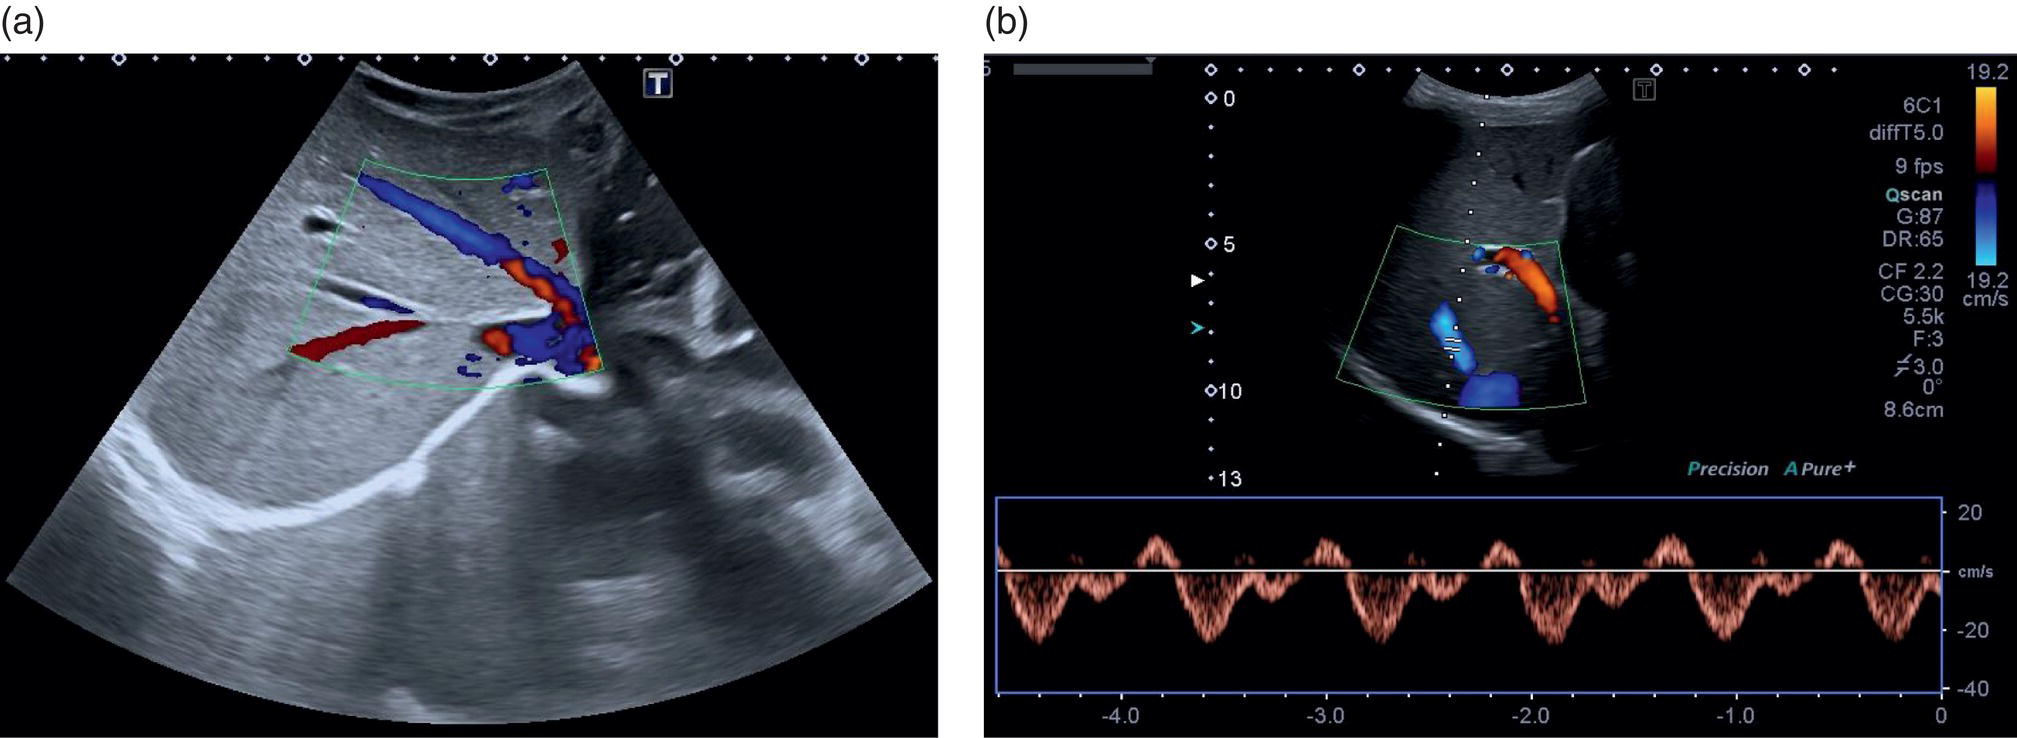

A more in‐depth assessment of the PV may be needed, and this is usually traced from the confluence of the superior mesenteric vein and splenic vein forming the main PV, as previously described. This should then be traced to its intrahepatic division into the main right and left lobes of the liver (Video 3.6). These vessels should be assessed with greyscale, colour, and spectral Doppler flow (see Chapter 1). Portal venous flow is usually monophasic or mildly phasic and hepatopetal in direction (Figure 3.36). Portal flow velocity may be influenced by obstruction and increased intrahepatic resistance, particularly in the presence of PV thrombosis and cirrhosis or severe heart failure/increased central venous pressure. In the latter case, the portal venous flow is typically pulsatile (see Chapters 8 and 12). ![]()

The confluence of the hepatic veins in the subcostal oblique view provides a good starting point to visualise their patency. From there the LHV, MHV, and RHV can be visualised along their entirety to the IVC with B‐mode and colour Doppler. These should also be assessed with spectral Doppler, best in the longitudinal plane, primarily to assess the flow phasicity (Figure 3.37) [9]. An assessment of the HA is usually not performed for routine clinical purposes. However, there has been much work assessing the Doppler flow of the HA in research studies for chronic liver disease [10–12]. The HA is typically visualised at the porta hepatis and in the longitudinal plane. A spectral Doppler trace allows measurement of the velocities and resistive index (Figure 3.38). Note that there are anatomical variants of the origin of the hepatic artery, which can be difficult to ascertain on occasion especially with ultrasound.